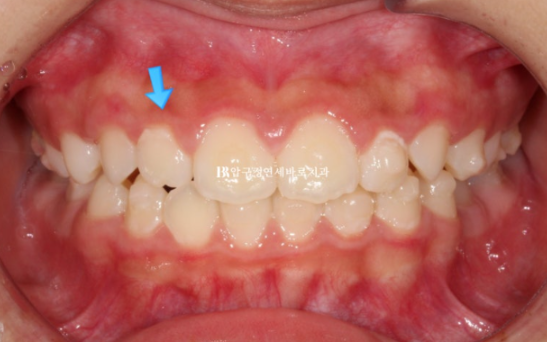

파란 화살표 측절치 치아는 아래와 거꾸로 물리는 반대교합입니다.

23.10

치아 나올 공간이 부족한 것은 아니여도 소량의 악궁확장을 통해 앞니 돌출을 어느정도 해소하기로 했습니다.

입술부전증이나 돌출을 완전히 해소하려면 나중에 발치교정이 필요할 수도 있지만 보호자가 비발치 치료를 원했습니다.

무턱 주걱턱 비대칭 등의 골격적 문제는 없었어서 바로 인비절라인 퍼스트 치료에 들어갔고 첫 장치를 끼기 시작한것은 23년 11월입니다.